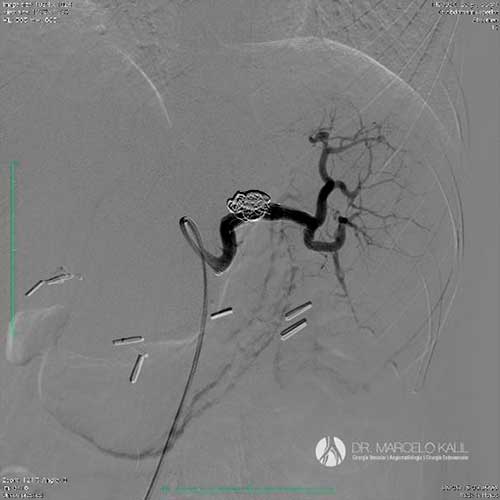

Dr. Marcelo Kalil

CRM 130623 | RQE 58565 | RQE 58565-1